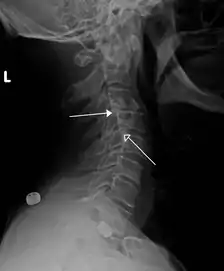

Класс 1 ретролистезы C3 на C4 и C4 на C5